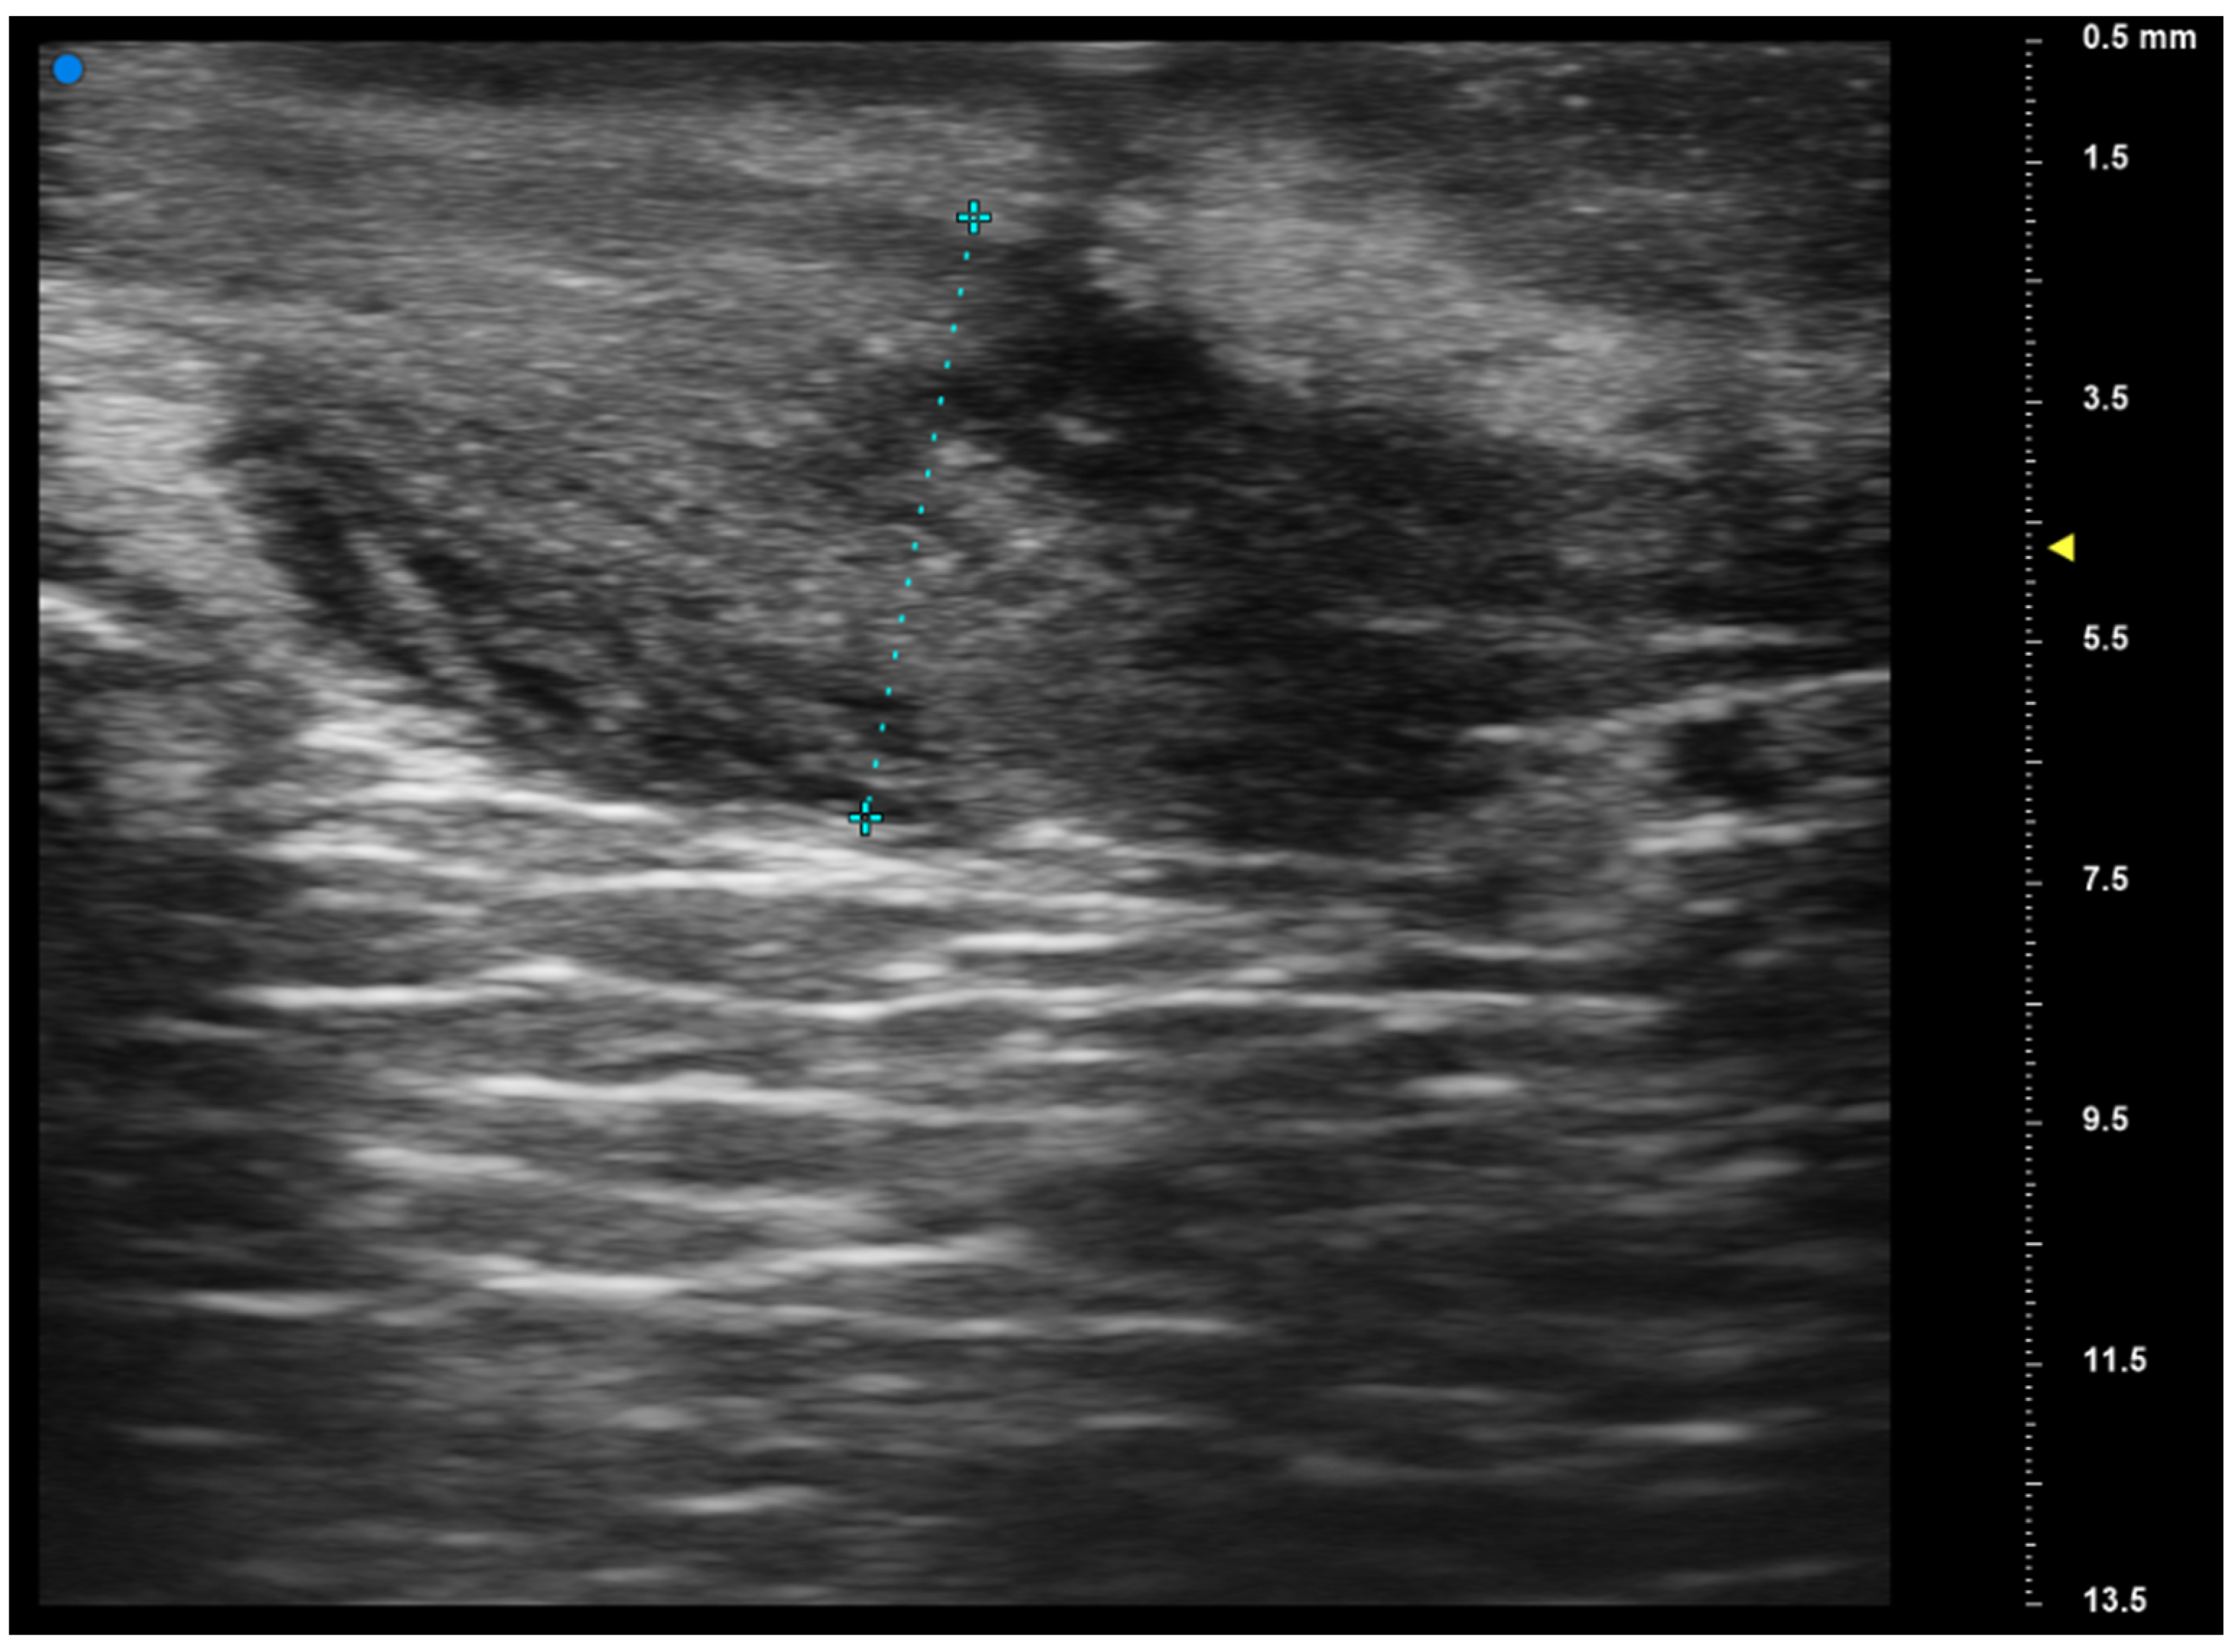

2.2. UHFUS Scan Protocol